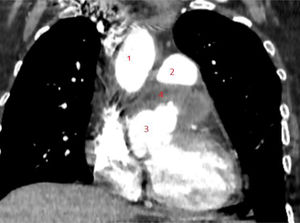

Realizamos una angiotomografía, la cual informó de un aneurisma de gran tamaño de seno de Valsalva izquierdo de 88,9 mm, que se encuentra por detrás del tronco de la arteria pulmonar y por delante de la aurícula izquierda. Se observa la coronaria izquierda saliendo en la porción distal del aneurisma. El cayado aórtico y la aorta descendente resultan con diámetros dentro de la normalidad (fig. 3).

Reconstrucción de tomografía donde se observa gran ASV izquierdo por detrás de la arteria pulmonar y por delante de la aurícula izquierda. 1) Aorta ascendente. 2) Tronco de arteria pulmonar. 3) ASV izquierdo. 4) Arteria coronaria izquierda. 5) Arteria coronaria derecha.

ASV: aneurisma de seno de Valsalva.